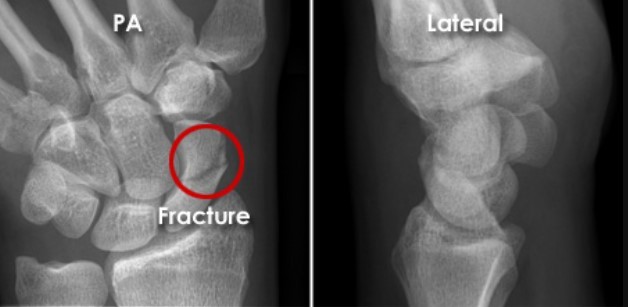

Patient presents with a sore wrist. They state that the got into a fight last night and despite remembering “knocking the f***** out” they can’t remember hurting their wrist. An X-ray of the wrist is provided below. What is the likely diagnosis?

Bennett’s fracture: Intra-articular fracture of 1st MC joint

Typically caused by fist fights

Triangular fragment at metacarpal base